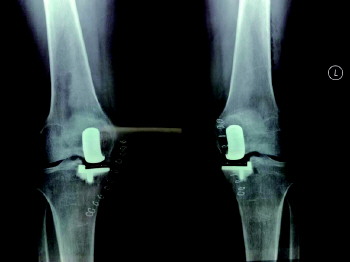

对膝关节骨性关节炎、股骨头坏死的治疗,采用分阶段阶梯治疗方案,包括保守运动康复疗法,中医中药疗法、生长因子注射、关节镜清理、半月板成形、截骨矫形、单髁置换、全膝关节置换等一系列疗法。

手术前

手术前后对比。

手术后